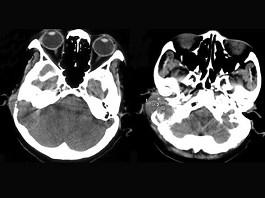

女,56岁,右侧中耳术后发现右外耳道新生物一年,PE:右外耳道内段被新生物充满,CT如图所示,应诊断为 ( )A、听神经瘤B、中耳结核...